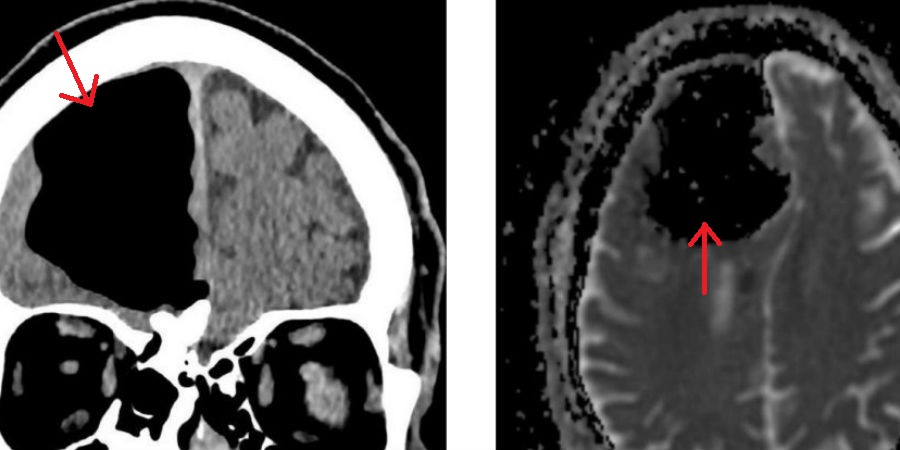

Omdat instabiliteit en halfzijdige zwakte vaak zijn geassocieerd met een beroerte, werd de man naar het ziekenhuis doorverwezen voor een CT-scan. Toen de artsen de resultaten van die scan zagen, waren ze met stomheid geslagen: op de plek waar normaal gesproken de rechter frontale hersenkwab zit, was nu een groot zwart gat te zien. Miste deze man een deel van zijn hersenen?

Om die bizarre diagnose uit te sluiten, maakten de dokters ook nog een MRI-scan van het hoofd van de Ier. En die wees uit dat beide hersenhelften van de man nog helemaal intact waren. Wat kon dan wel het zwarte gat op de CT-scan verklaren?

Een pneumatocoele, ook wel een luchtzak genoemd is de boosdoener. Dit verschijnsel ontstaat vaak als gevolg van verwondingen aan het gezicht, luchtweginfecties, of bij mensen die een operatie hebben ondergaan voor schedelbasistumoren. Maar geen van deze gebeurtenissen bleek de reden te zijn voor de luchtzak in het hoofd van de 84-jarige patiënt.

Wat wél de reden is, is een osteoom: een goedaardige bottumor op het zeefbeen (dat de neusholte van de hersenen scheidt). Door deze tumor is een deel van het zeefbeen weggesleten, waardoor lucht de schedel in wordt geduwd resulterend in een luchtzak.